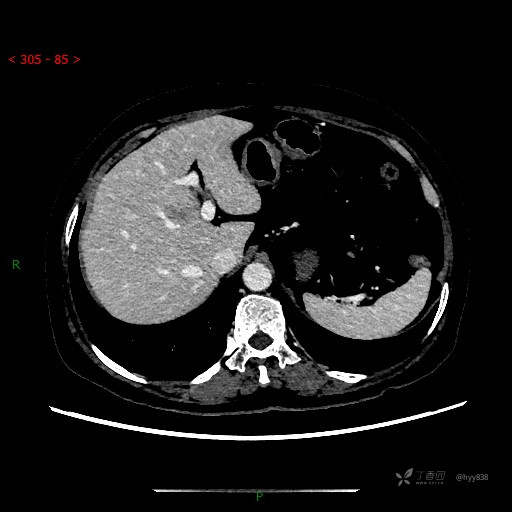

上腹部CT平扫